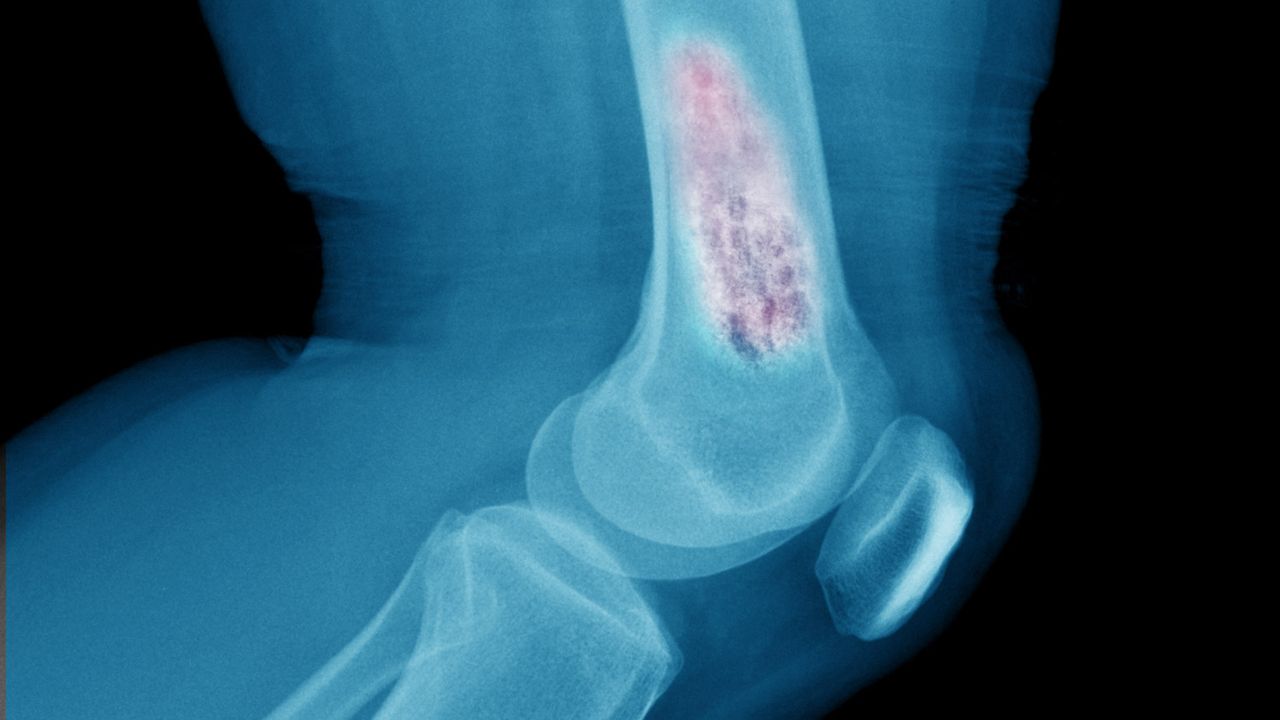

Hastalığın genellikle 50 yaş üstü bireylerde görüldüğünü ancak bazı risk faktörleriyle 40'lı yaşlarda da ortaya çıkabileceğini belirten Prof. Dr. Aydın, "Osteoporoz sessiz ilerler. Kırık oluşmadan fark edilmeyebilir. Kemik yapısı bozulur, gözenekli hale gelir. Vücut eski kemiği yenisiyle değiştiremez. Bu nedenle erken teşhis çok önemlidir" ifadelerini kullandı.